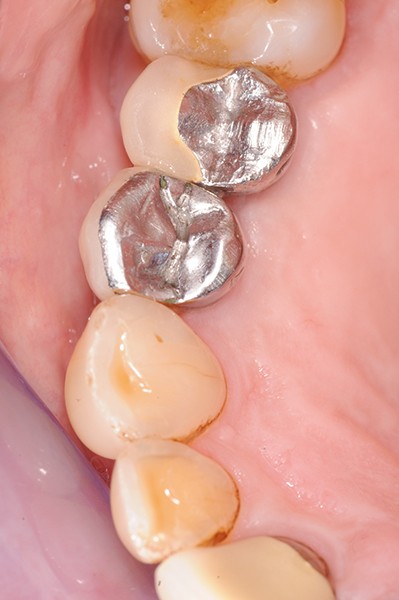

Lors de la maintenance de 2016, le contrôle de plaque de la patiente est toujours excellent et les tissus implantaires ne présentent pas de signes inflammatoires(fig. 2a et b).